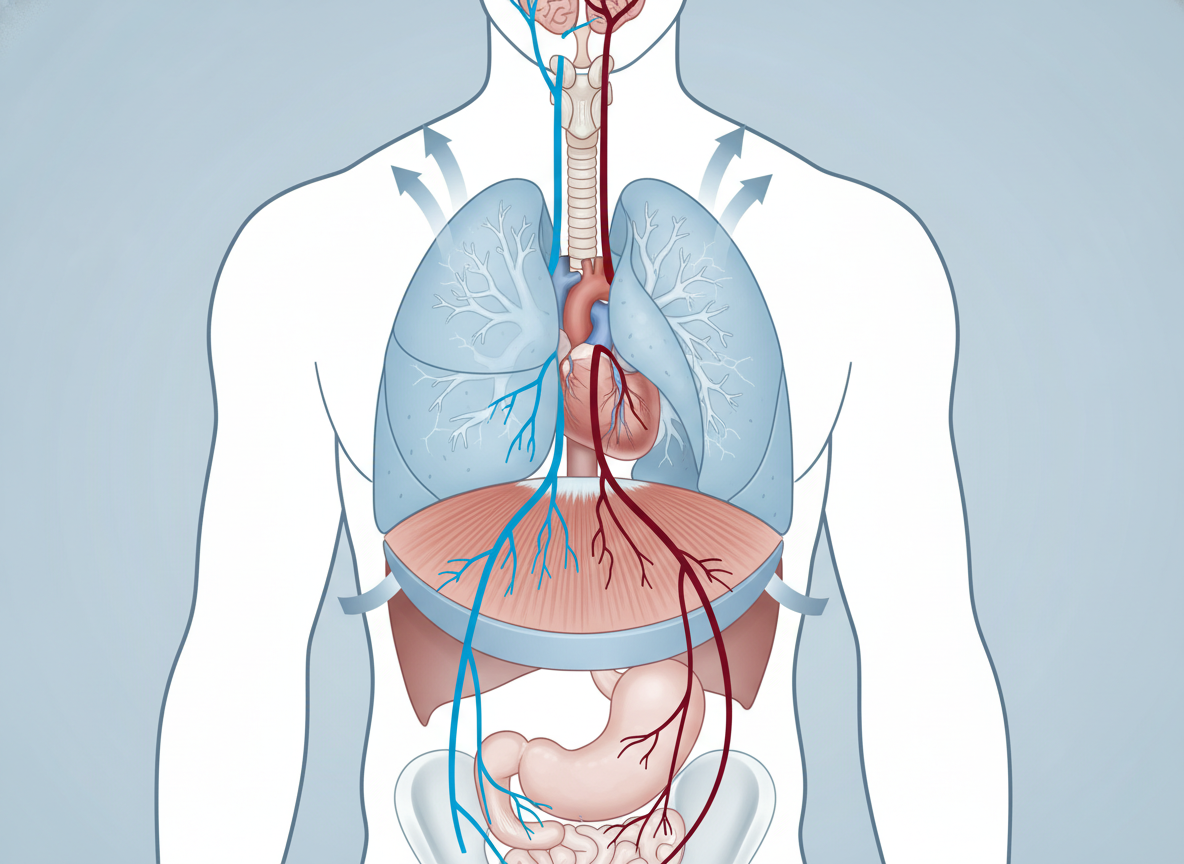

딸꾹질은 의외로 우리 몸의 아주 특별한 근육, 바로 횡격막의 비자발적인 경련 때문에 발생해요. 이 횡격막이 갑자기 수축하면서 폐로 공기가 빠르게 들어오고, 이때 성대가 닫히면서 '히끅' 하는 소리가 나는 거죠. 생각해 보면 정말 신기한 현상이죠?

주로 미주신경이나 횡격막 신경이 자극을 받을 때 이런 현상이 나타나는데, 사실 대부분은 크게 걱정할 필요 없는 일시적인 경우가 많아요. 제가 겪어본 바로는 너무 급하게 식사를 하거나, 갑자기 차가운 음료를 마시거나, 스트레스를 많이 받으면 여지없이 딸꾹질이 찾아오곤 하더라고요.

횡격막 신경(Phrenic nerve)이나 미주신경(Vagus nerve) 손상으로 인해 딸꾹질이 발생할 수도 있어요. 목 부위의 종양이나 염증, 심지어는 귀 질환도 신경을 자극할 수 있답니다. 정말 예민한 우리 몸의 신경계인 것 같아요.